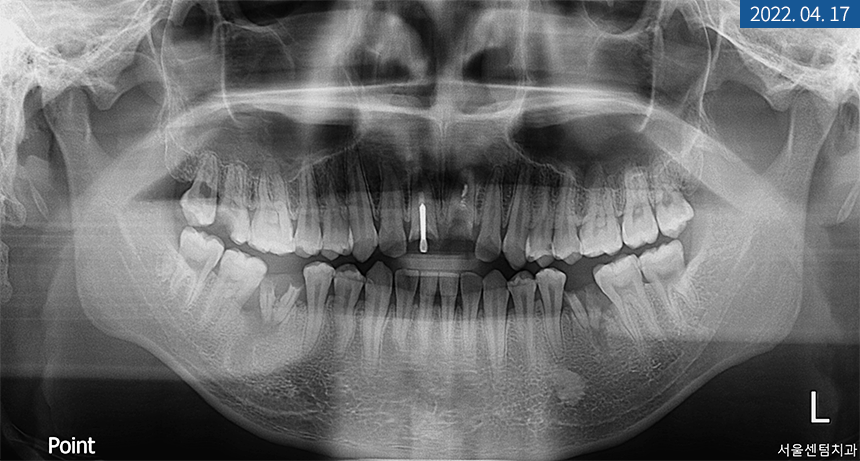

20대 남성분의 X-ray 사진

X-ray 상 앞니 손상과 치근 염증이

심하다는 결과를 봐서는 발치가 필요해 보였으며

좌측 하악 어금니도 뿌리 밑에 염증이 생겨

치아 보존이 힘든 상황이었습니다.

그만큼 치아 강직과 만성 복합치주염으로 인한

난발치 상황이었죠.

우측도 파열돼있었지만

우선 치주 치료를 하면서 지켜봐도

좋을 것 같다는 판단이 들었습니다.